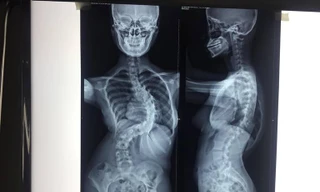

TPO - Dù được phát hiện bệnh từ năm 11 tuổi, nhưng tình hình vẹo cột sống của thiếu nữ vẫn không cải thiện sau 4 năm. Bệnh nhân nhập viện điều trị khi cột sống đã vẹo đến 110 độ, uốn lượn như xương rắn.

TPO - Hai năm trước, trong một lần được khám sức khỏe tại trường học, nữ sinh được phát hiện bị chứng vẹo cột sống nặng khiến tay, chân dài hơn bình thường. Dù bệnh nhân đã được chạy chữa nhiều nơi nhưng tình trạng không khả quan hơn.